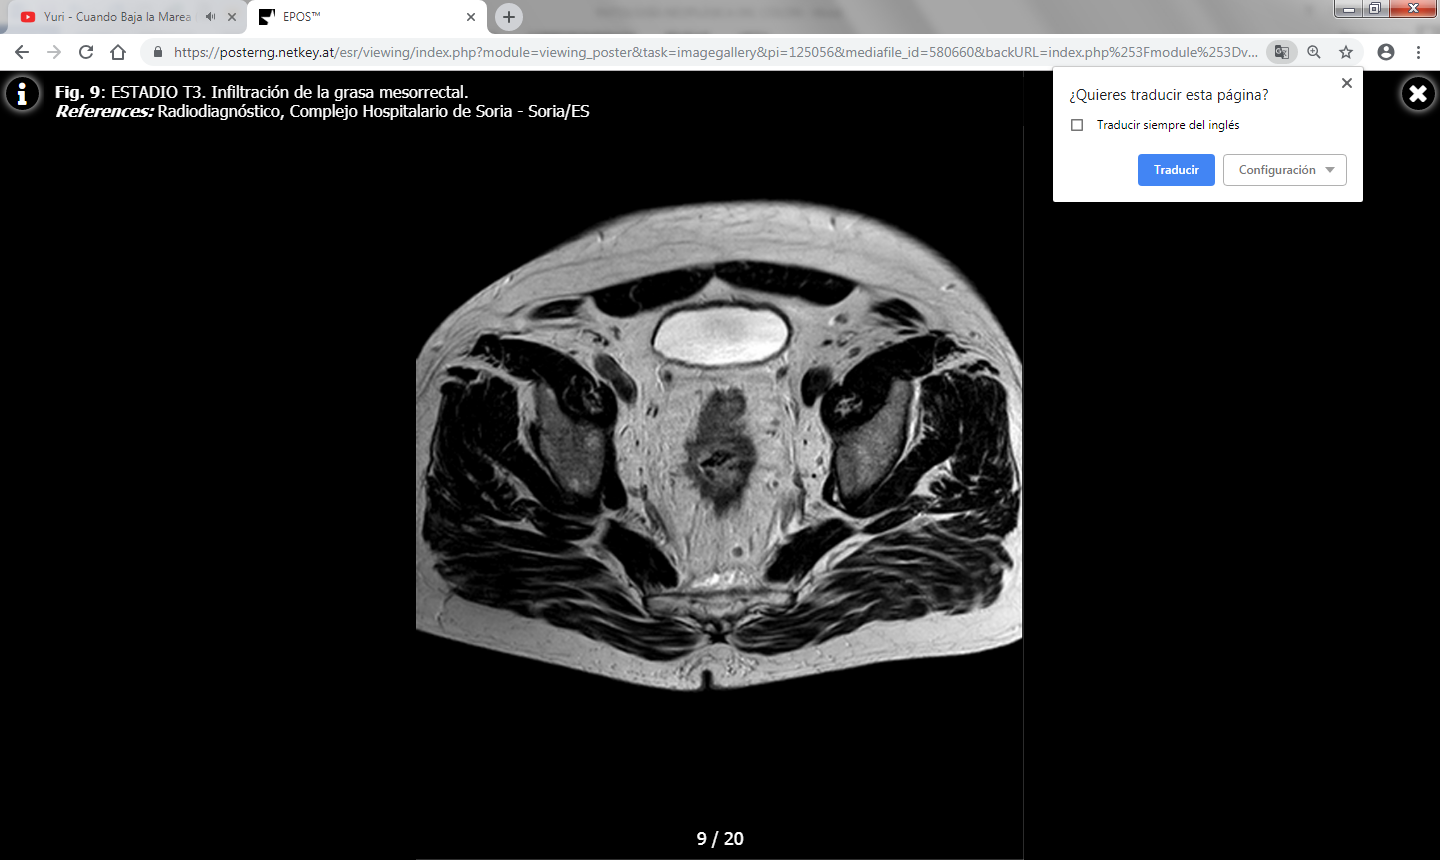

La TC juega un papel importante en el estudio de extensión del carcinoma colorrectal y en la detección de recurrencias.

Los hallazgos en TC incluyen una masa de densidad de partes blandas de contornos irregulares o un engrosamiento parietal focal asimétrico que condicionan estenosis de la luz colónica. Las masas de mayor tamaño pueden presentar un centro necrótico de baja atenuación y ocasionalmente pueden contener gas.